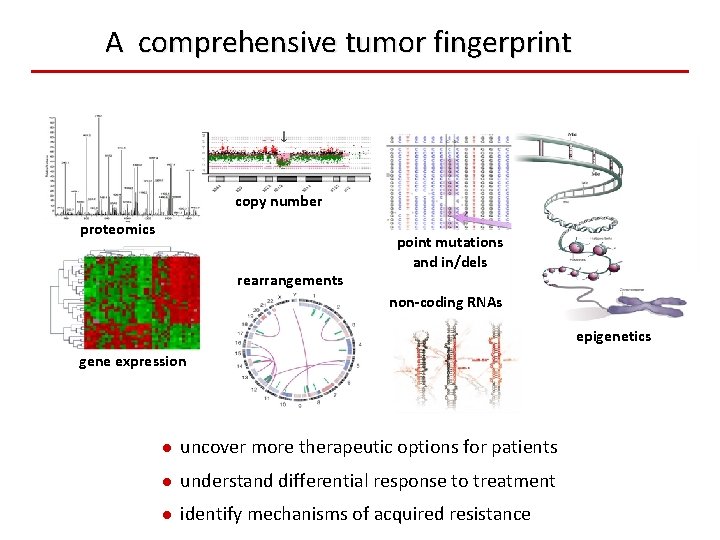

A comprehensive tumor fingerprint copy number proteomics rearrangements point mutations and in/dels non-coding RNAs epigenetics gene expression ● uncover more therapeutic options for patients ● understand differential response to treatment ● identify mechanisms of acquired resistance